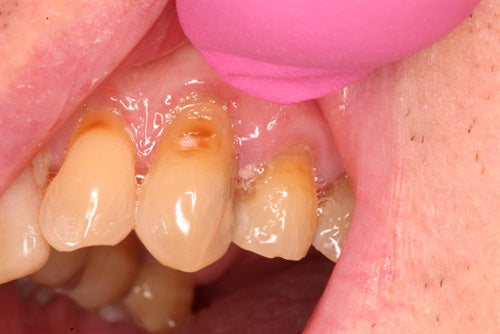

Dahl technique Doc Terry style by Dr. Ahmad Fayad

Introduction: 40 year old female on a tight budget and is slowly losing her teeth. She was referred to me by another patient who had the same style buildups. Decided... Read More